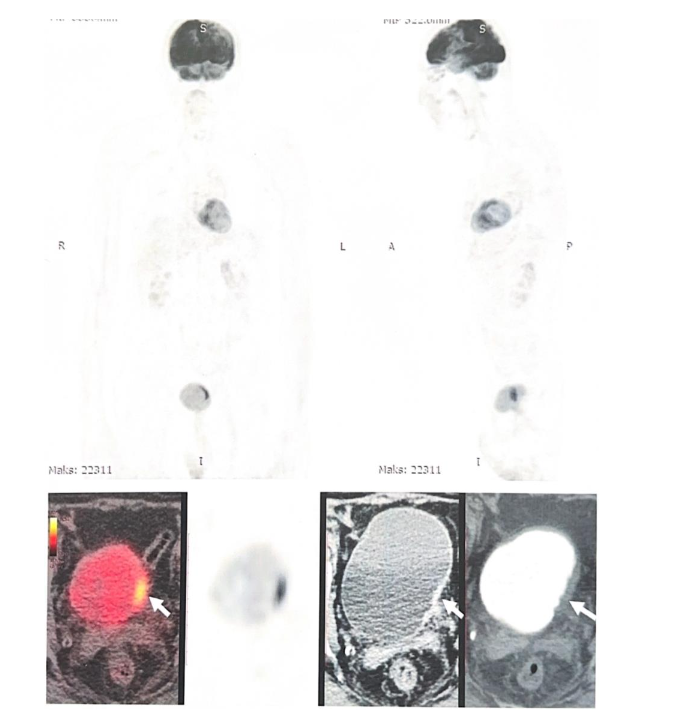

Since completing definitive therapy, the patient has been monitored annually with whole-body PET/CT.

To date, there is no evidence of recurrence of either the primary pulmonary adenocarcinoma or the secondary bladder carcinoma. More than 10 years after initial diagnosis, the patient remains clinically stable and continues maintenance therapy with Erlotinib (150 mg/day). Annual whole-body PET/CT imaging continues to demonstrate complete remission with no evidence of disease recurrence or progression.

Importantly, the persistence of the EGFR exon 19 deletion was confirmed twice (between 2020 and 2024) through circulating tumor DNA (ctDNA) analysis of peripheral blood using real time PCR and a portable LAMP system, the Doctor Vida® device (STAB VIDA, Caparica, Portugal). No emergent resistance mutations have been detected, supporting the continued efficacy of long-term EGFR-targeted therapy.